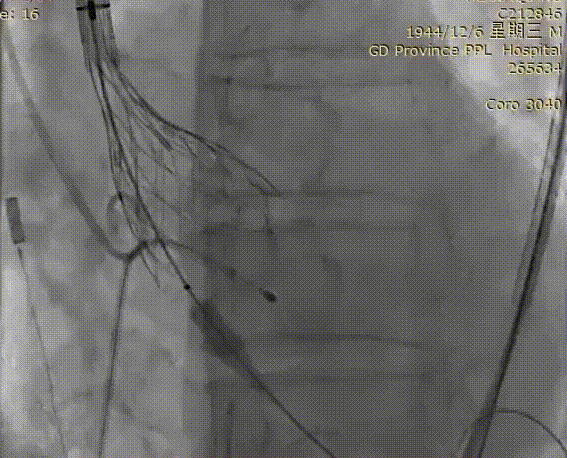

术后造影

术后

瓣膜位置形态良好,跨瓣压差消失,无瓣周漏,手术效果非常好。

交换猪尾测得跨瓣压差

动脉压力115/60mmHg

左心室压力120/4mmHg

术后压差5mmHg